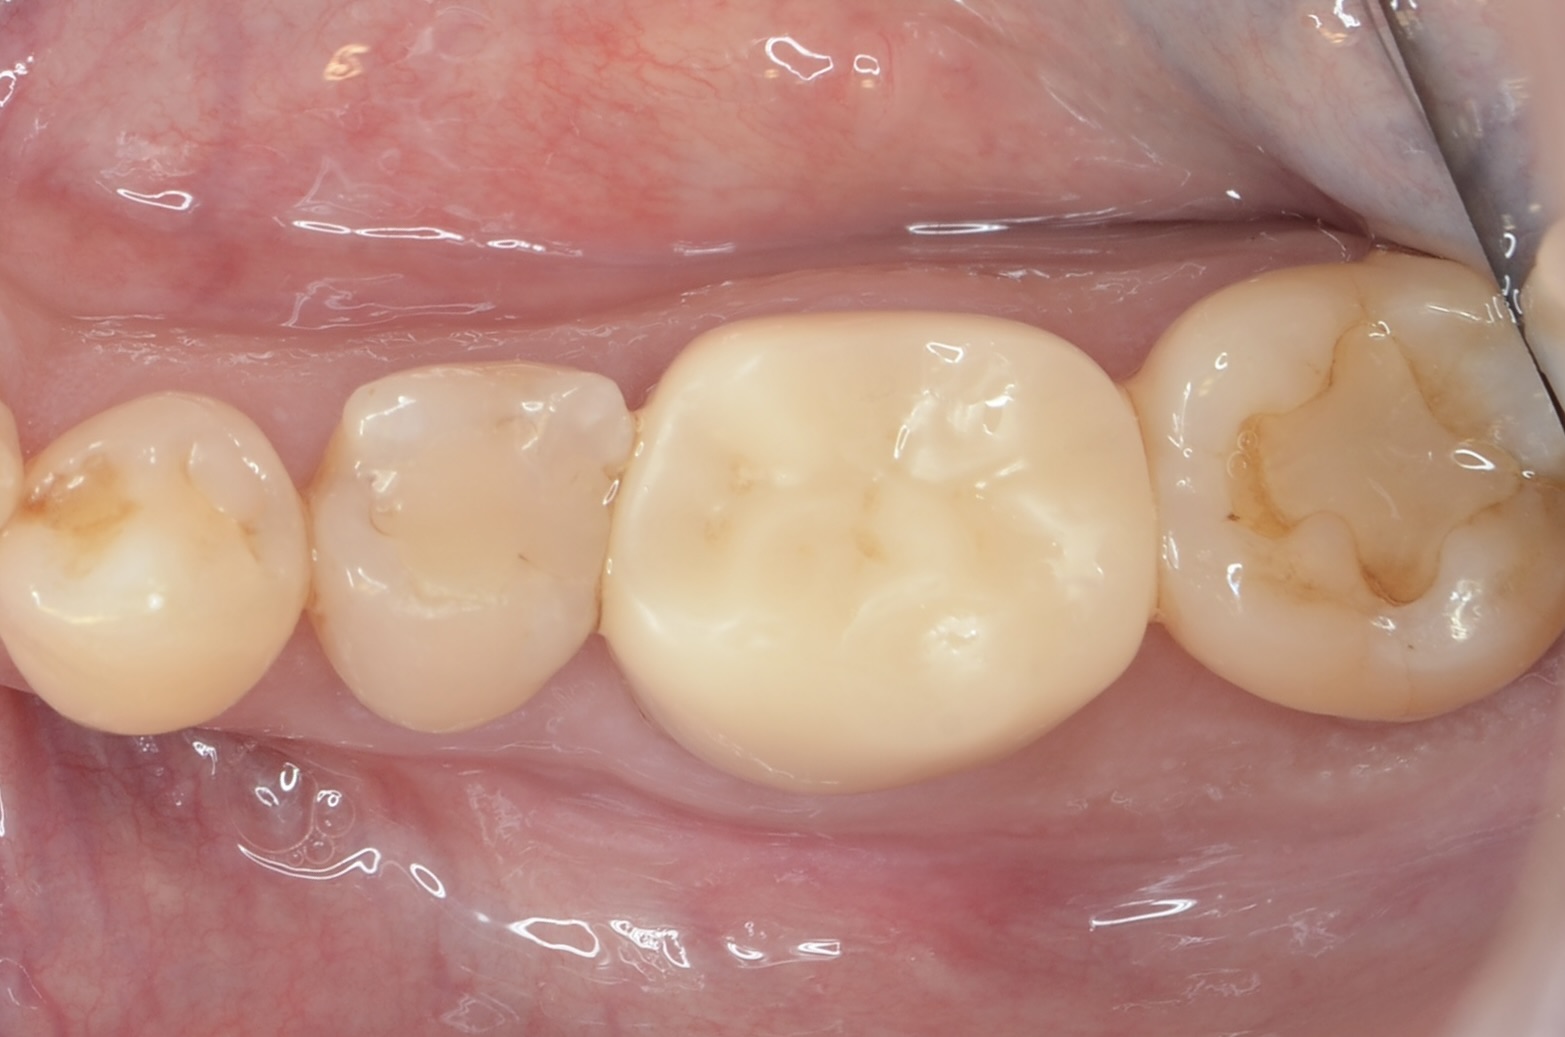

側方面観

自然で綺麗です。 -